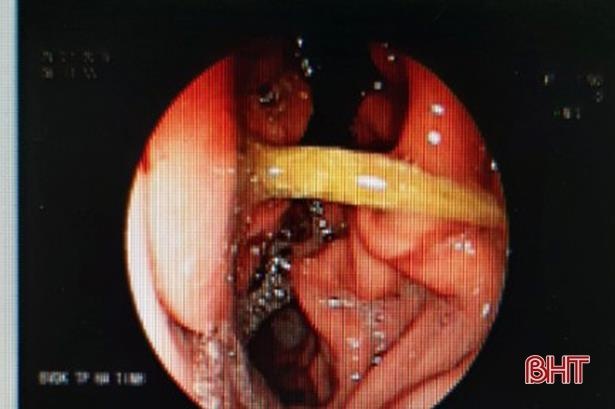

| Cây tăm nhọn cắm ngang dạ dày người bệnh. Ảnh: Báo Hà Tĩnh. |

“Từ hình ảnh nội soi, ê-kíp phát hiện có dị vật ở dạ dày. Khi bơm rửa sạch, đó là cây tăm nhọn cắm ngang dạ dày”, BS Khiêm cho biết.

Lúc 8h sáng nay (29/7), ê-kíp đã nội soi gắp que tăm ra khỏi dạ dày cho người bệnh.